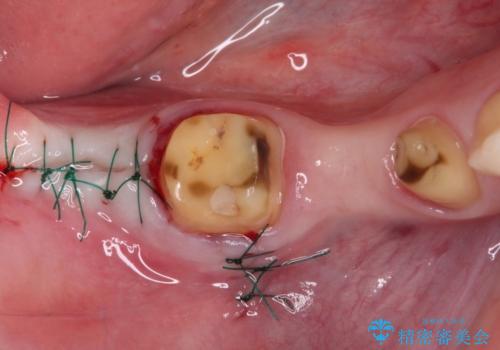

- 近医で奥歯が割れているので抜歯が必要と言われたとのことで来院された患者様です。

診断の結果、歯根が縦に破折しており抜歯が必要な状態でした。

抜歯してからインプラント埋入までには時間がかかるため、その間に下顎左右臼歯の金属のブリッジをオールセラミックへ変えていくこととしました。